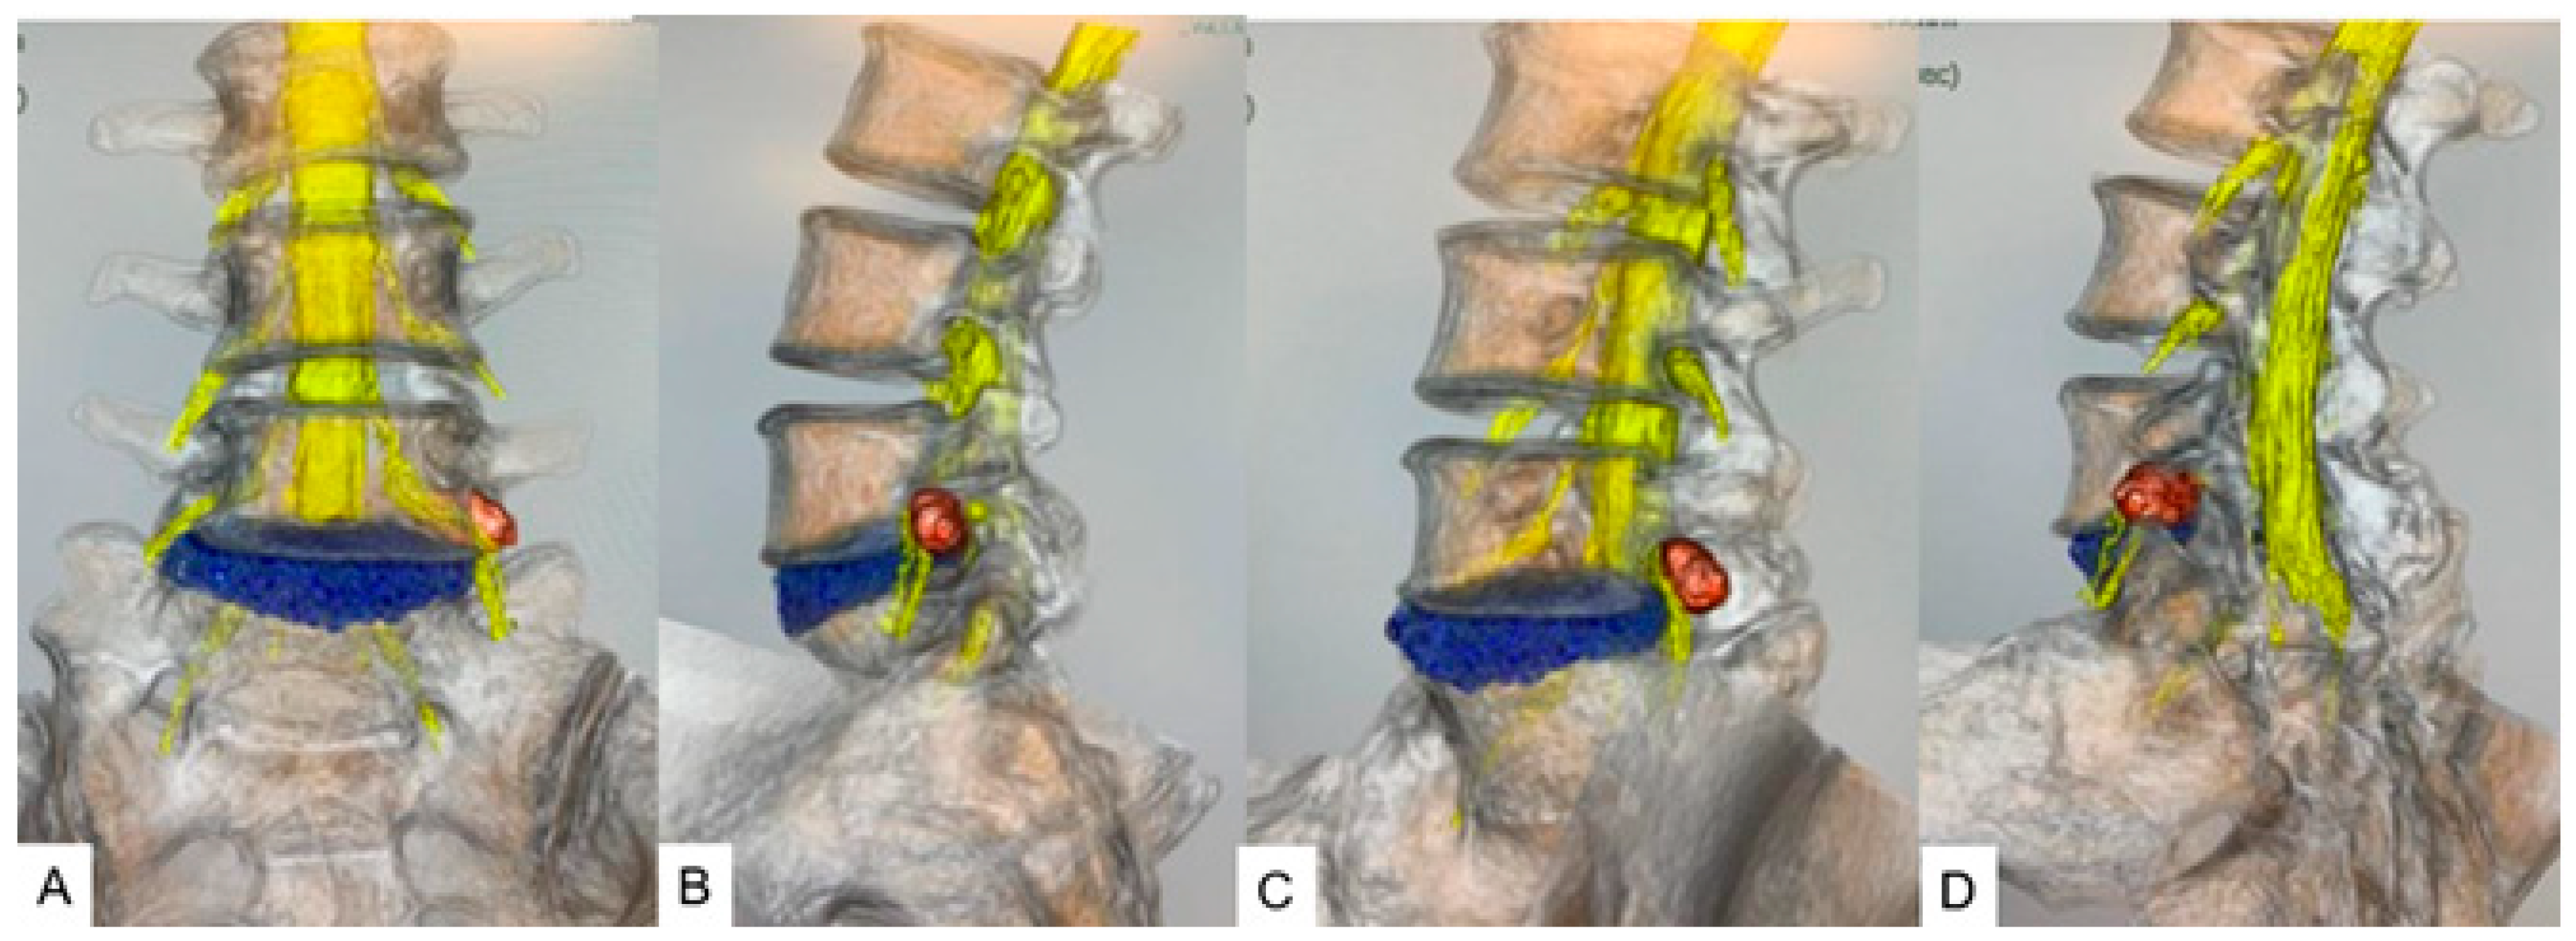

CT/MRI fusion imaging integrates the high bony resolution of CT with the superior soft tissue contrast of MRI. This technique provides comprehensive images for diagnostic and intraoperative guidance for evaluating disk herniation and vascular anatomy with bony structures [50,51]. Computer-generated three-dimensional (3D) fused models facilitate immersive preoperative planning (Figure 5).

Figure 5. A 46-year-old male, left L5/S1 foraminal/extraforaminal disk herniation. (A) Anterior view. (B) Lateral view. (C) Anterior oblique view. (D) Posterior oblique view. Reprinted with permission from Ref. [50].